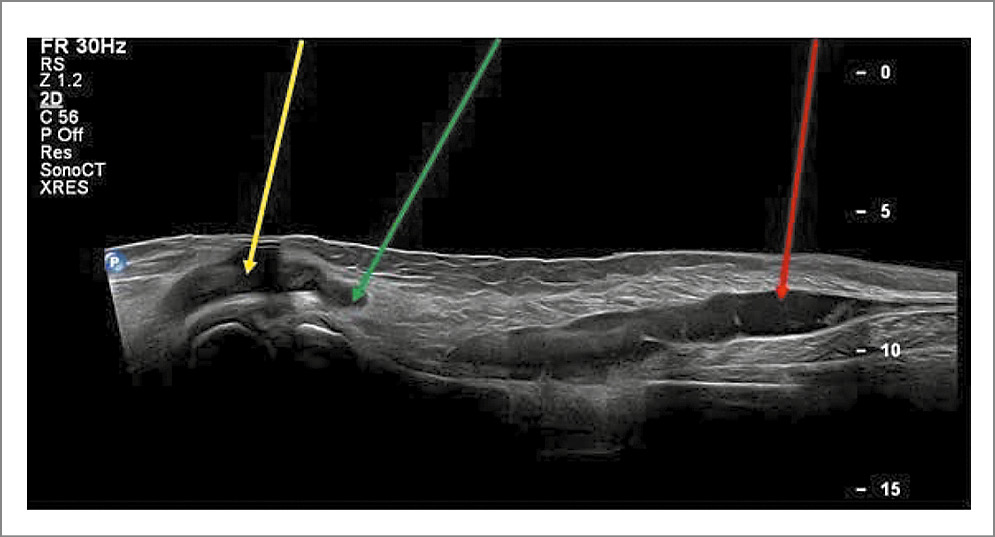

Наиболее доступным и эффективным методом верификации разрыва КБ является ультразвуковое исследование, которое позволяет визуализировать такие характерные признаки, как неоднородность структуры и деформация (заострение) нижнего полюса КБ, а также появление субфасциальных жидкостных прослоек вдоль сухожилия и/или брюшка медиальной головки икроножной мышцы (рис. 1, 2).

Рис. 2. Разрыв КБ. Распространение содержимого в межфасциальное пространство заднего отдела голени (красная стрелка). Остаточное содержимое в кисте (желтая стрелка). Зона разрыва (зеленая стрелка).